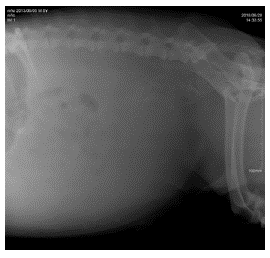

Se realiza ecografía focalizada para trauma abdominal (AFAST, por sus siglas en inglés) (Boysen y Lisciandro 2013) como prueba para el reconocimiento temprano de líquido libre en el abdomen, que en este caso arroja un resultado positivo para la presencia de líquido abdominal en las cuatro ventanas. Posteriormente, se realiza abdominocentesis con el paciente en decúbito lateral derecho para lavado y colecta de líquido peritoneal y se determina el valor de creatinina, cuyo resultado es de 8 mg/dl. Se lleva a cabo un lavado peritoneal con cloruro de sodio 0,9% con el fin de estabilizar al paciente y luego se procede a realizar una radiografía simple (figura 1), una uretrocistografía retrograda (figura 2) con medio de contraste positivo, en este caso iopramida (Ultravist®), en la cual se observa la disrupción uretral y zonas radiopacas en abdomen compatibles con la presencia de medio de contraste en el abdomen caudal, cuyo resultado es positivo para ruptura uretral. Se toman muestras de sangre para cuadro hemático y química sanguínea (ALT, creatinina, potasio, albúmina, calcio) en el que se observan como anormalidades el aumento de creatinina en valores de 2,5 mg/dL y anemia normocítica hipocrómica. No fueron autorizadas la totalidad de los exámenes solicitados. Se realiza un electrocardiograma en el cual no se encuentran anormalidades. Se sugiere la realización de laparotomía exploratoria para verificar daños adyacentes y ubicar y reparar el sitio exacto donde se produjo el rompimiento del tracto urinario inferior.

Fuente: elaboración propia.

FIGURA 1 Proyección latero-lateral izquierda/ derecha de abdomen. En la imagen se observa pérdida de la diferenciación del contorno de los órganos abdominales, densidad radiopaca compatible con líquido libre en el abdomen.